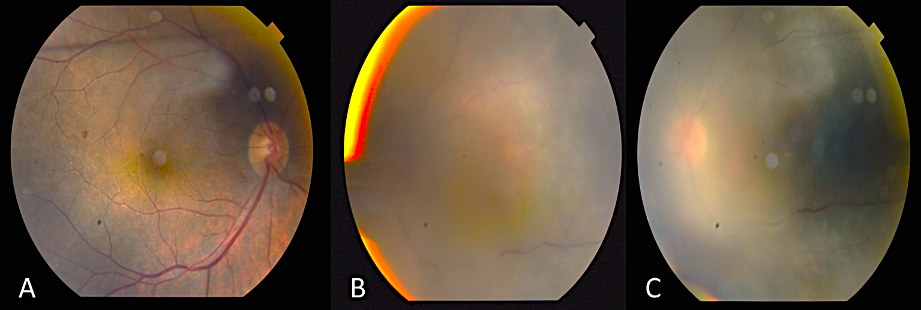

Since the visual acuity decreased to hand motion during systemic investigations, systemic steroid treatment was initiated with isoniazid (INH) prophylaxis. Following treatment, the vitreous inflammation in the left eye improved from +4 to +2 cells, allowing improved visualization of the posterior segment. The optic nerve appeared hyperemic and infiltrated, and the retina demonstrated diffuse white infiltrates with associated generalized retinal thickening, vascular sheathing, and venous beading, predominantly in the left eye (Figure 2 [Fig. 2]). Optical coherence tomography (OCT) showed irregularities and multiple subretinal hyperreflective deposits in the retinal pigment epithelium and Bruch membrane level, which were predominantly present in the left eye and severe optic disc edema (Figure 3 [Fig. 3]). Fundus fluorescein angiography (FFA) revealed indistinct granular changes and mild disc staining in the right eye. Active lesions were characterized by a typical early hypofluorescent pattern observed in the retinal infiltrates, with late hyperfluorescence containing dilated retinal vessels, diffuse pinpoint leakage at the infiltrative border in the left eye and areas of capillary dropout were observed (Figure 4 [Fig. 4]).

Figure 2: Color photograph of both fundi post systemic steroid treatment with isoniazid prophylaxis

The optic nerve appeared hyperemic and infiltrated, and the retina demonstrated diffuse white infiltrates with associated generalized retinal thickening, vascular sheathing, and venous beading, predominantly in the left eye (A–C).